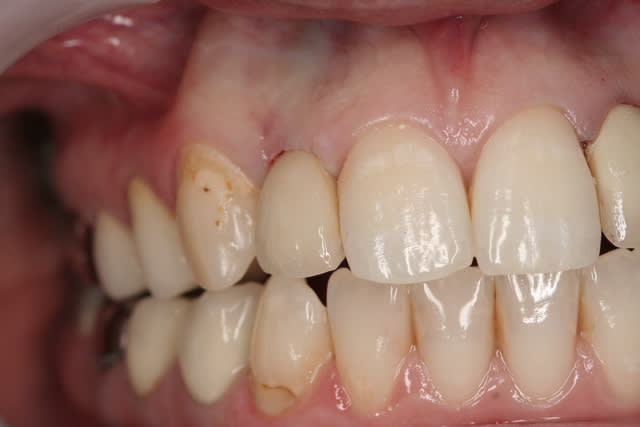

01/09/2010 à 16h54

-1 ou 2 mois plus tard ( je sais plus)

- empreinte avec transfert pop in

- pilier zircone esthétique Axiom

- prothèse et pilier

- pilier zircone en place

- couronne en place (petite compression gingivale)

fin du traitement

tu as perdu un peu d'os au col, ça serait du à l'expansion ????